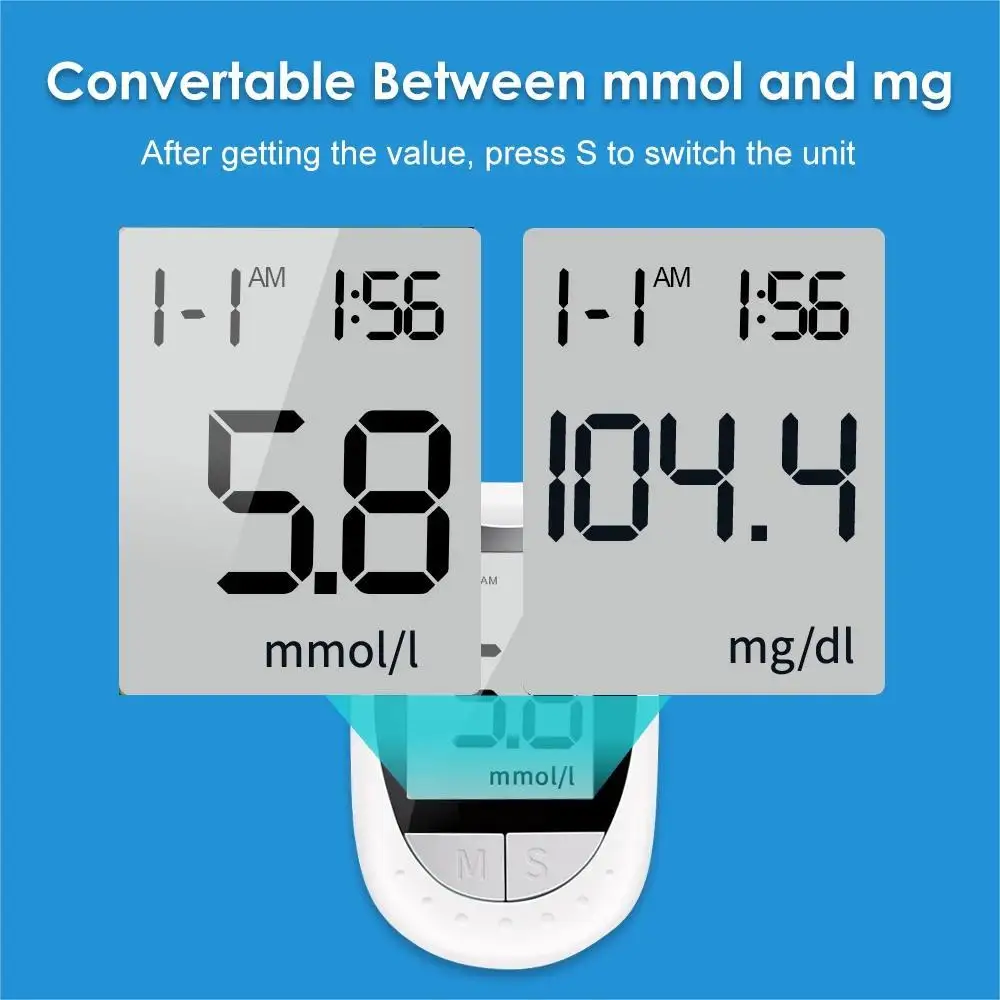

Units: mmol/L and mg/dl

Test range: 1.1-33.3 mmol/L (20-600mg/dl)